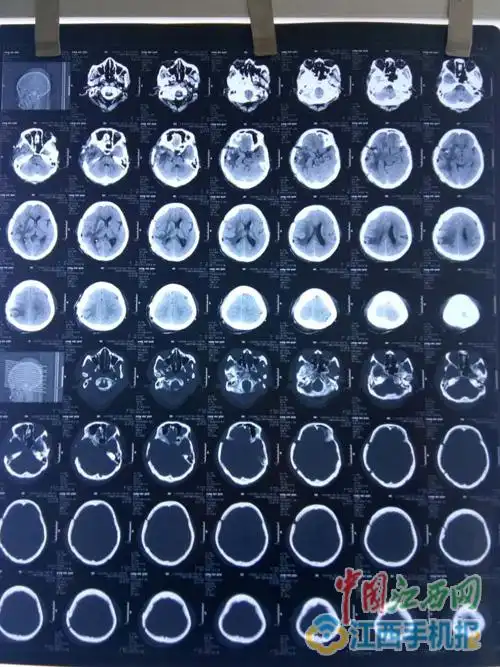

患者术后第二天头颅ct检查结果